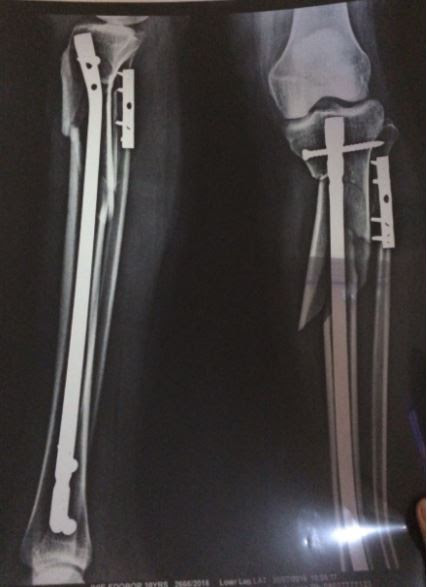

By that time I couldn’t stand up and my leg was bleeding profusely. I was rushed to the hospital where my jeans was torn off my leg to see the nature of my injury. The injury was so severe that my broken bone torn through my skin puncturing an artery in the process.

Almost 3months and 2 surgeries later, I have titanium plates and screws to keep my leg in place and I am unable to use my right leg. I still have my 3 children to care for and my life is at a stand still. The perpetuator was charged to court and released on bail 3 days later. Now he moves around freely carrying on with his life. Now is it wrong for me to cry for Justice.